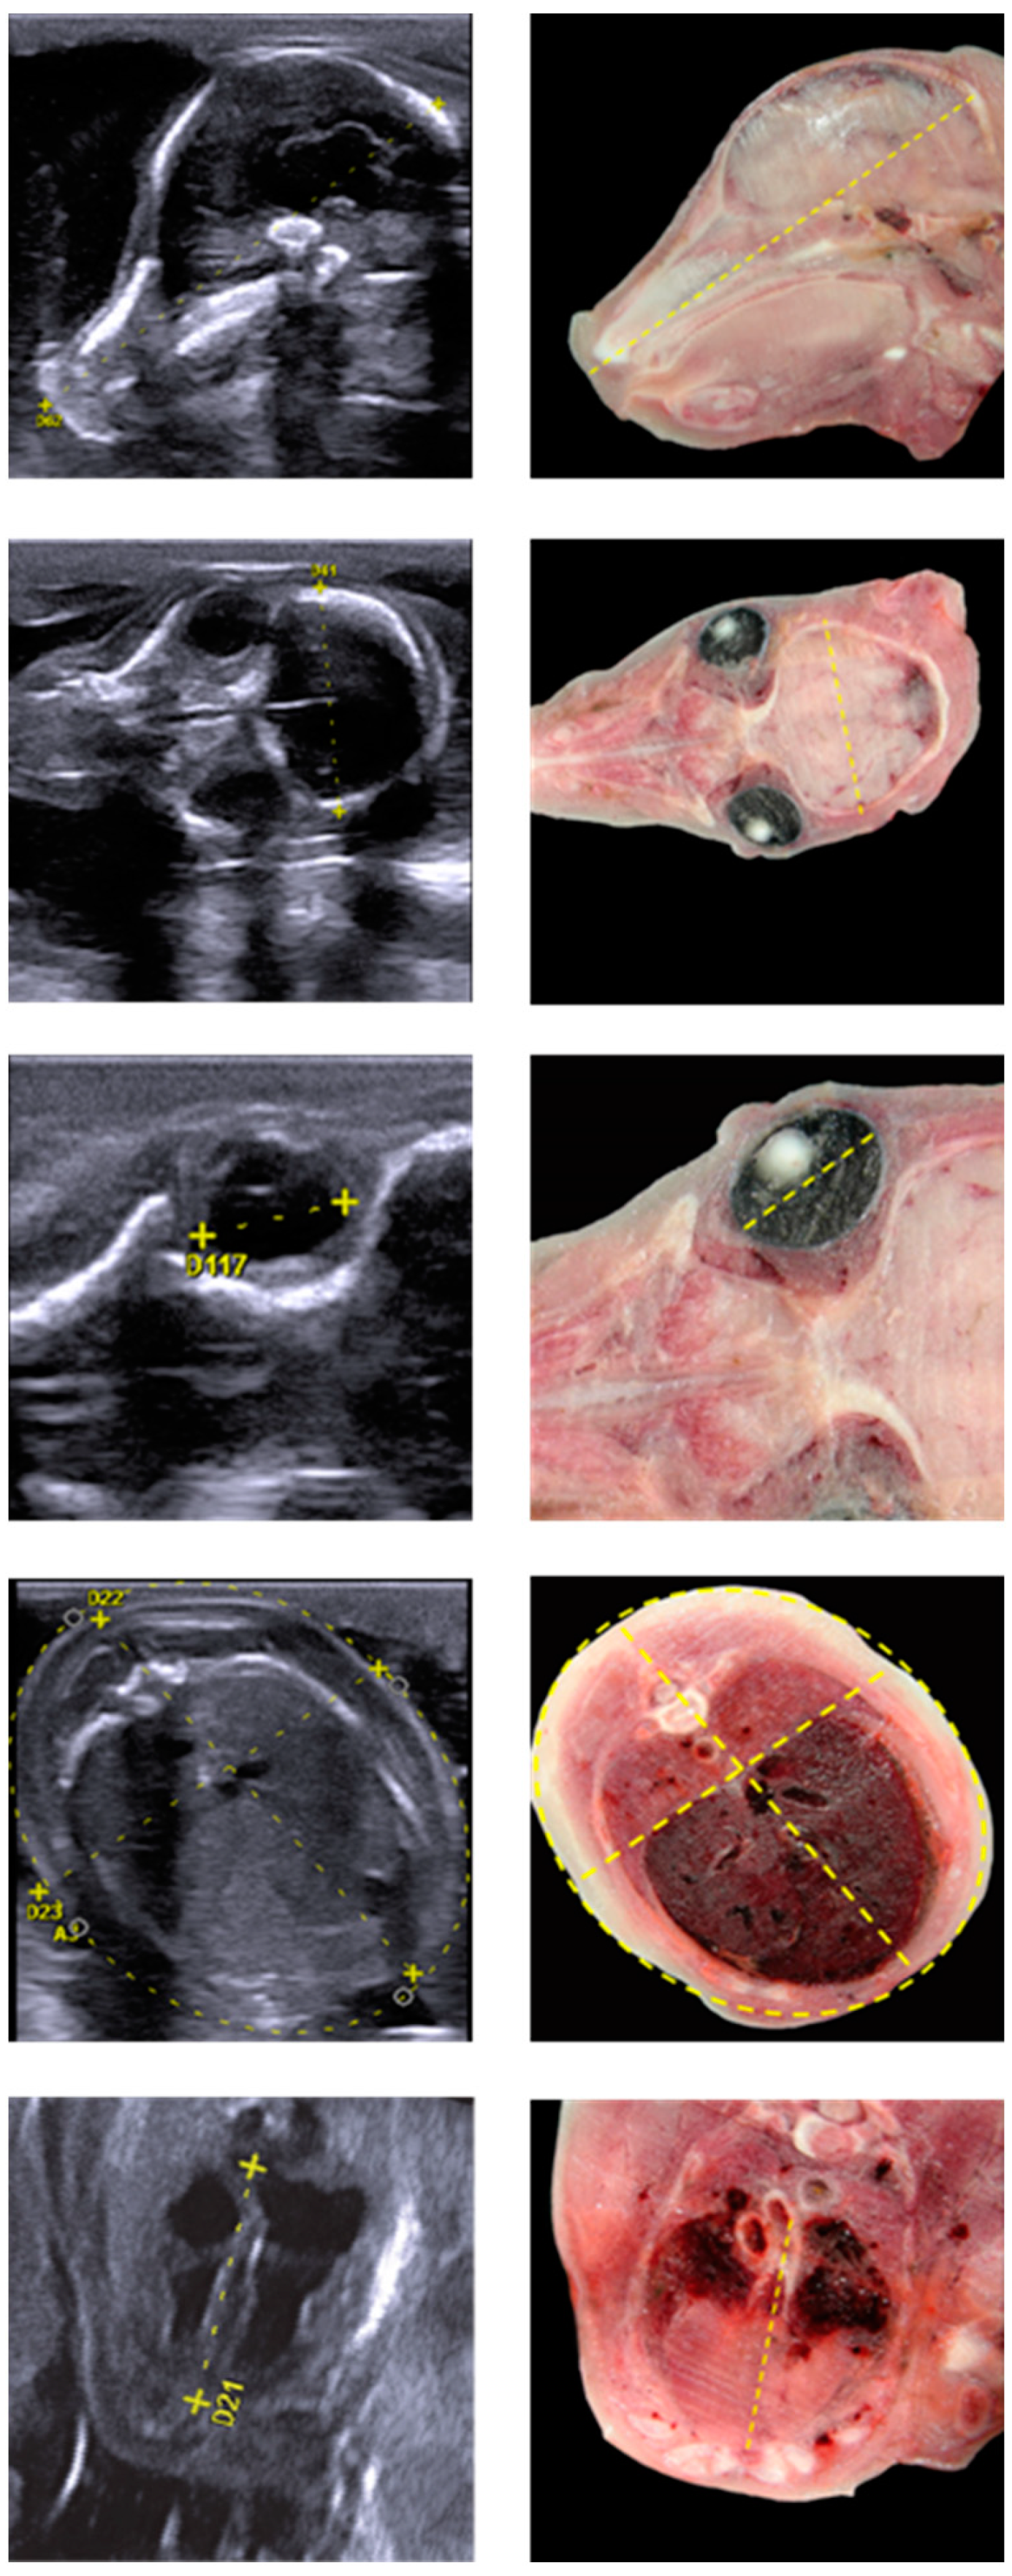

2.2. Ultrasound Measurements

3.2. Transabdominal Ultrasound Scan